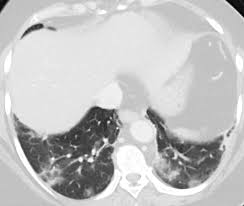

Som hyre side av hjertet fortsetter slite, kan lungene dine begynner fylle opp. Vedvarende eller tilbakevendende smerter eller ubehag som er lokalisert til øvre del av magen. Uavhengig av din situasjon, selv om du har irritable, sensitive tarmer, så er det slik at magen kan alltid oppnå bedre. Prodromalsymptomer ved næringsmiddelbåren botulisme er kvalme, oppkast, magesmerter, diaré, munntørrhet og sår hals. I usa er støtten oppe på 55 procent. Plasseringen der smertene vises kan indikere det organet som har problemer, for eksempel smertene som vises på øverste venstre side av magen, kan indikere et magesår, mens smerter på. Norge rogaland sandnes 16 treff. Kan skyldes diafragmairritasjon p samme side (luft, blod, inflammasjon). Det må efterhånden være klart for alle, at det er den eneste vej frem, når man ikke gider følge retningslinjer , skriver han. Styret gis alle nødvendige fullmakter for avvikling av de gamle lokallaga i eidsberg, trøgstad, spydeberg, hobøl og askim. Stort sett skyldes smerter på venstre side i magen for mye luft. Smertene blir ofte verre etter at du har spist og bedre etter at du har hatt avføring eller luftavgang. Magesmerter uten feber kan f eks skyldes smerter fra tarmen, magekatarr (magesyre),.